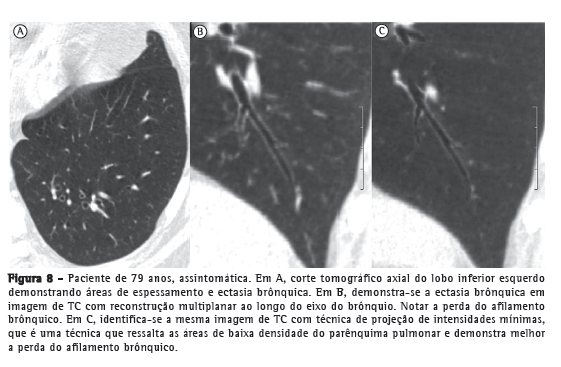

No estudo por TC do parênquima pulmonar, identificam-se alguns achados radiológicos muito comuns em idosos, e especula-se que eles tenham relação com as alterações do colágeno. Esses achados são atelectasias laminares, na maioria das vezes posteriores e basais, localizadas em áreas pendentes dos pulmões (Figura 5); espessamentos lineares subpleurais (Figura 6); áreas de aprisionamento aéreo (Figura 7); espessamento e ectasia brônquica (Figura 8); e cistos pulmonares.(41,50-53)